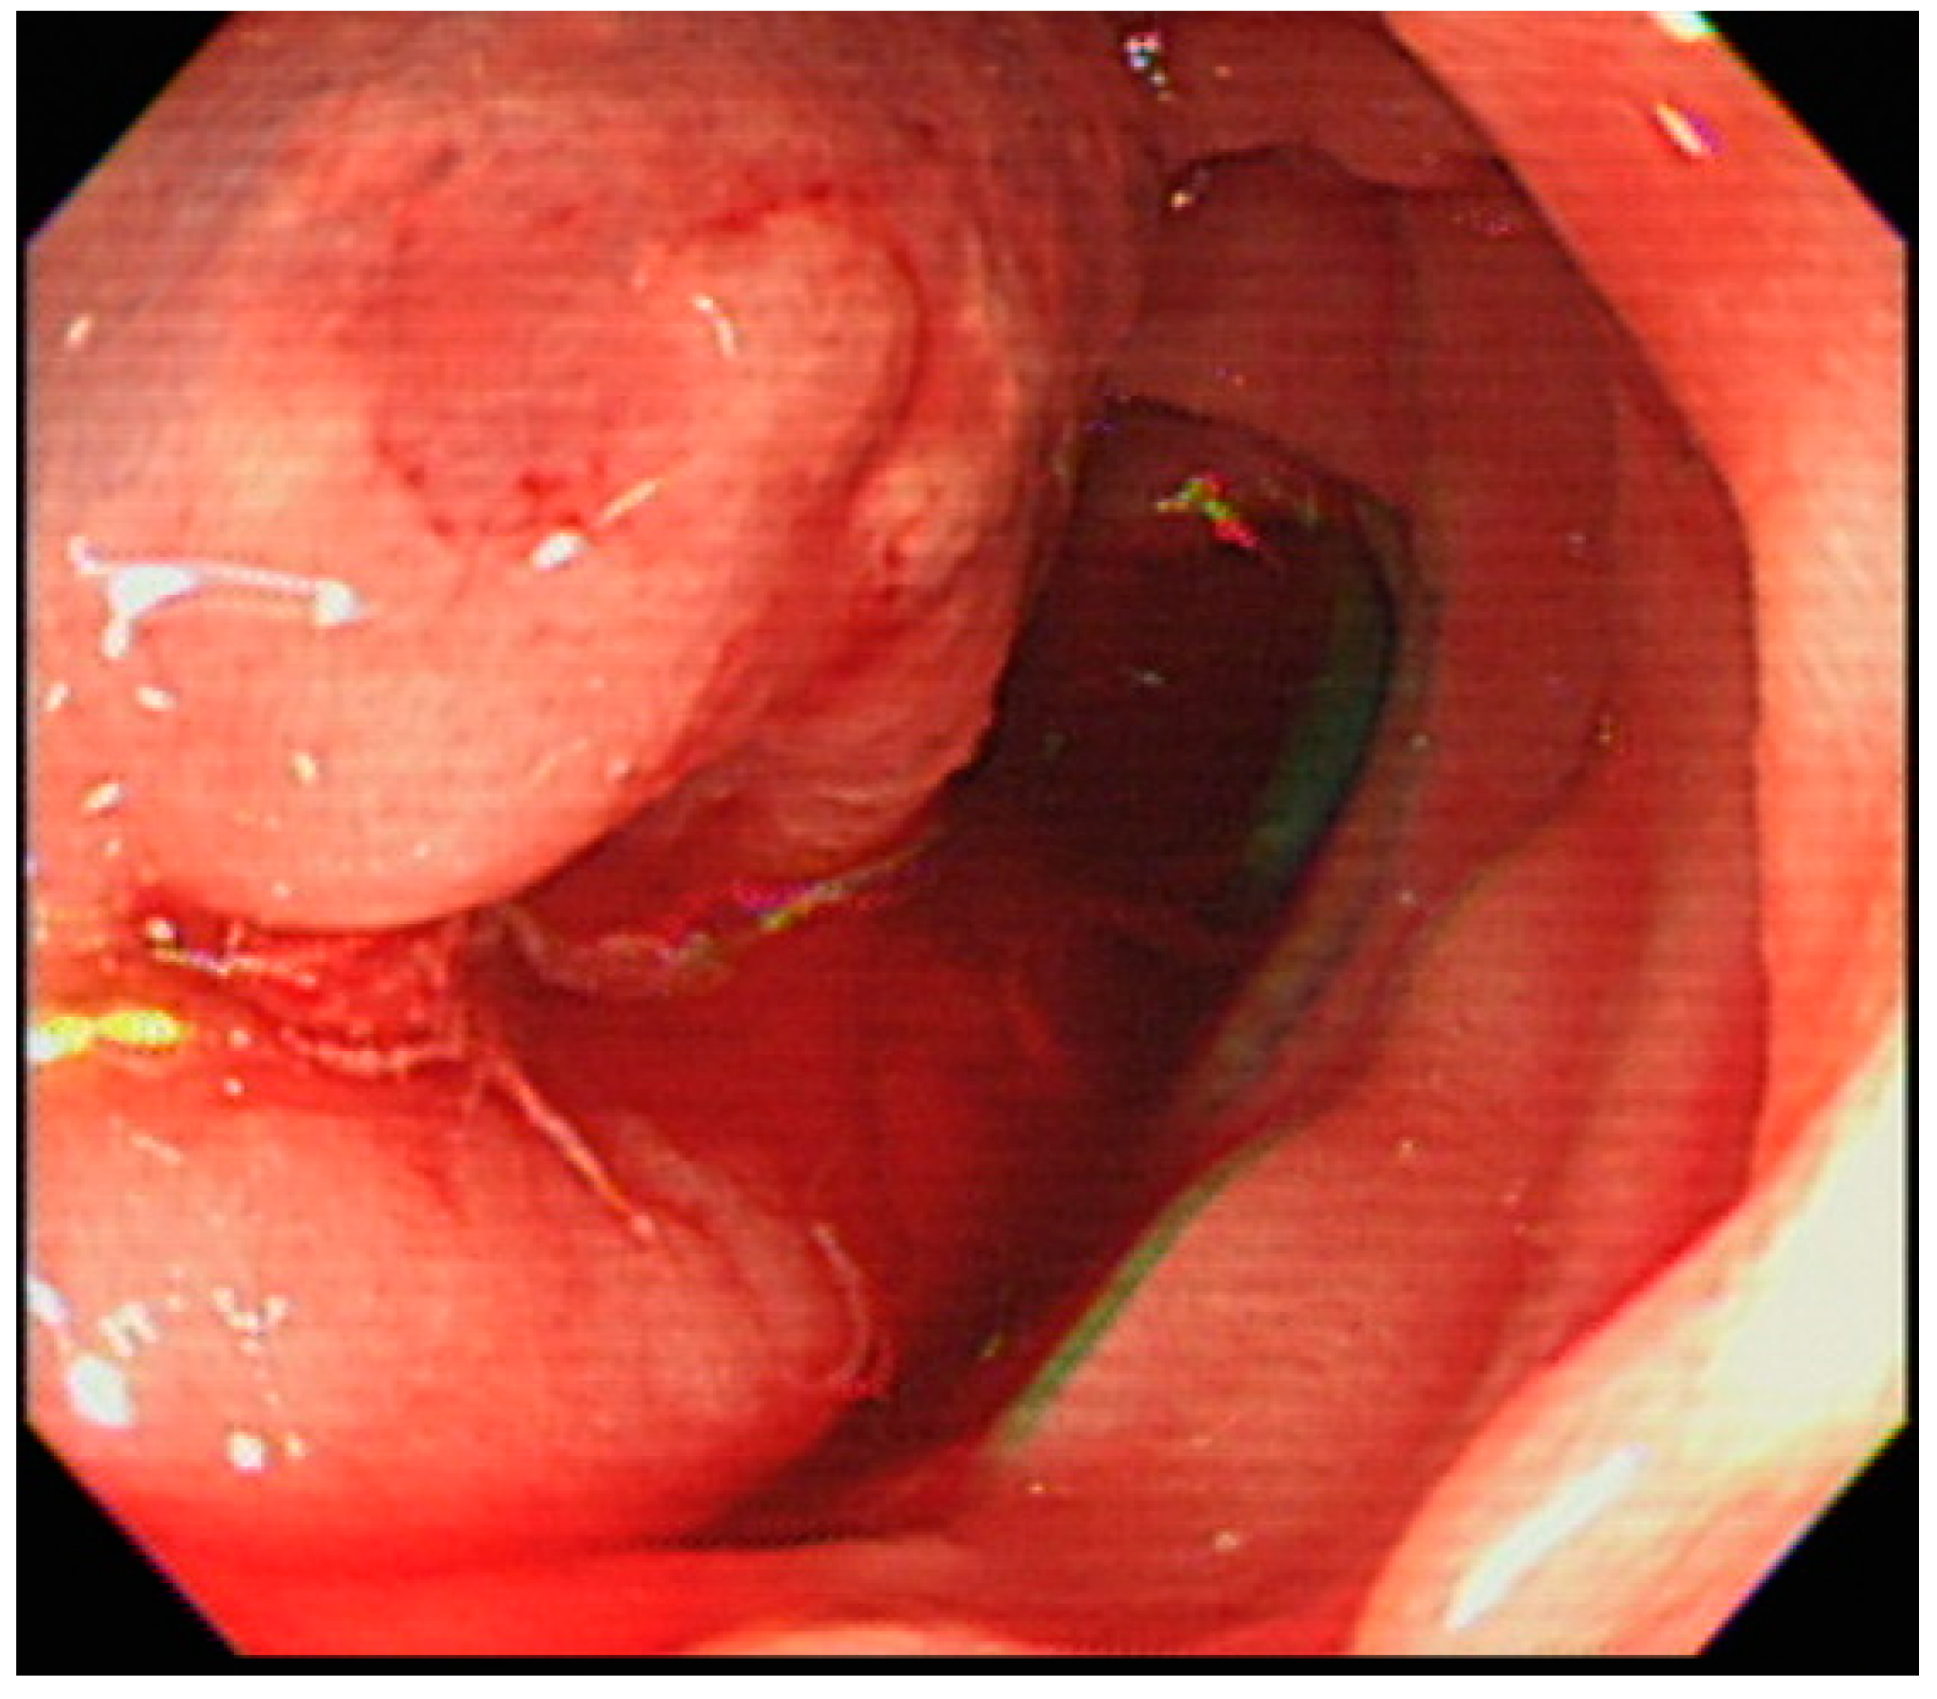

2. Case Report